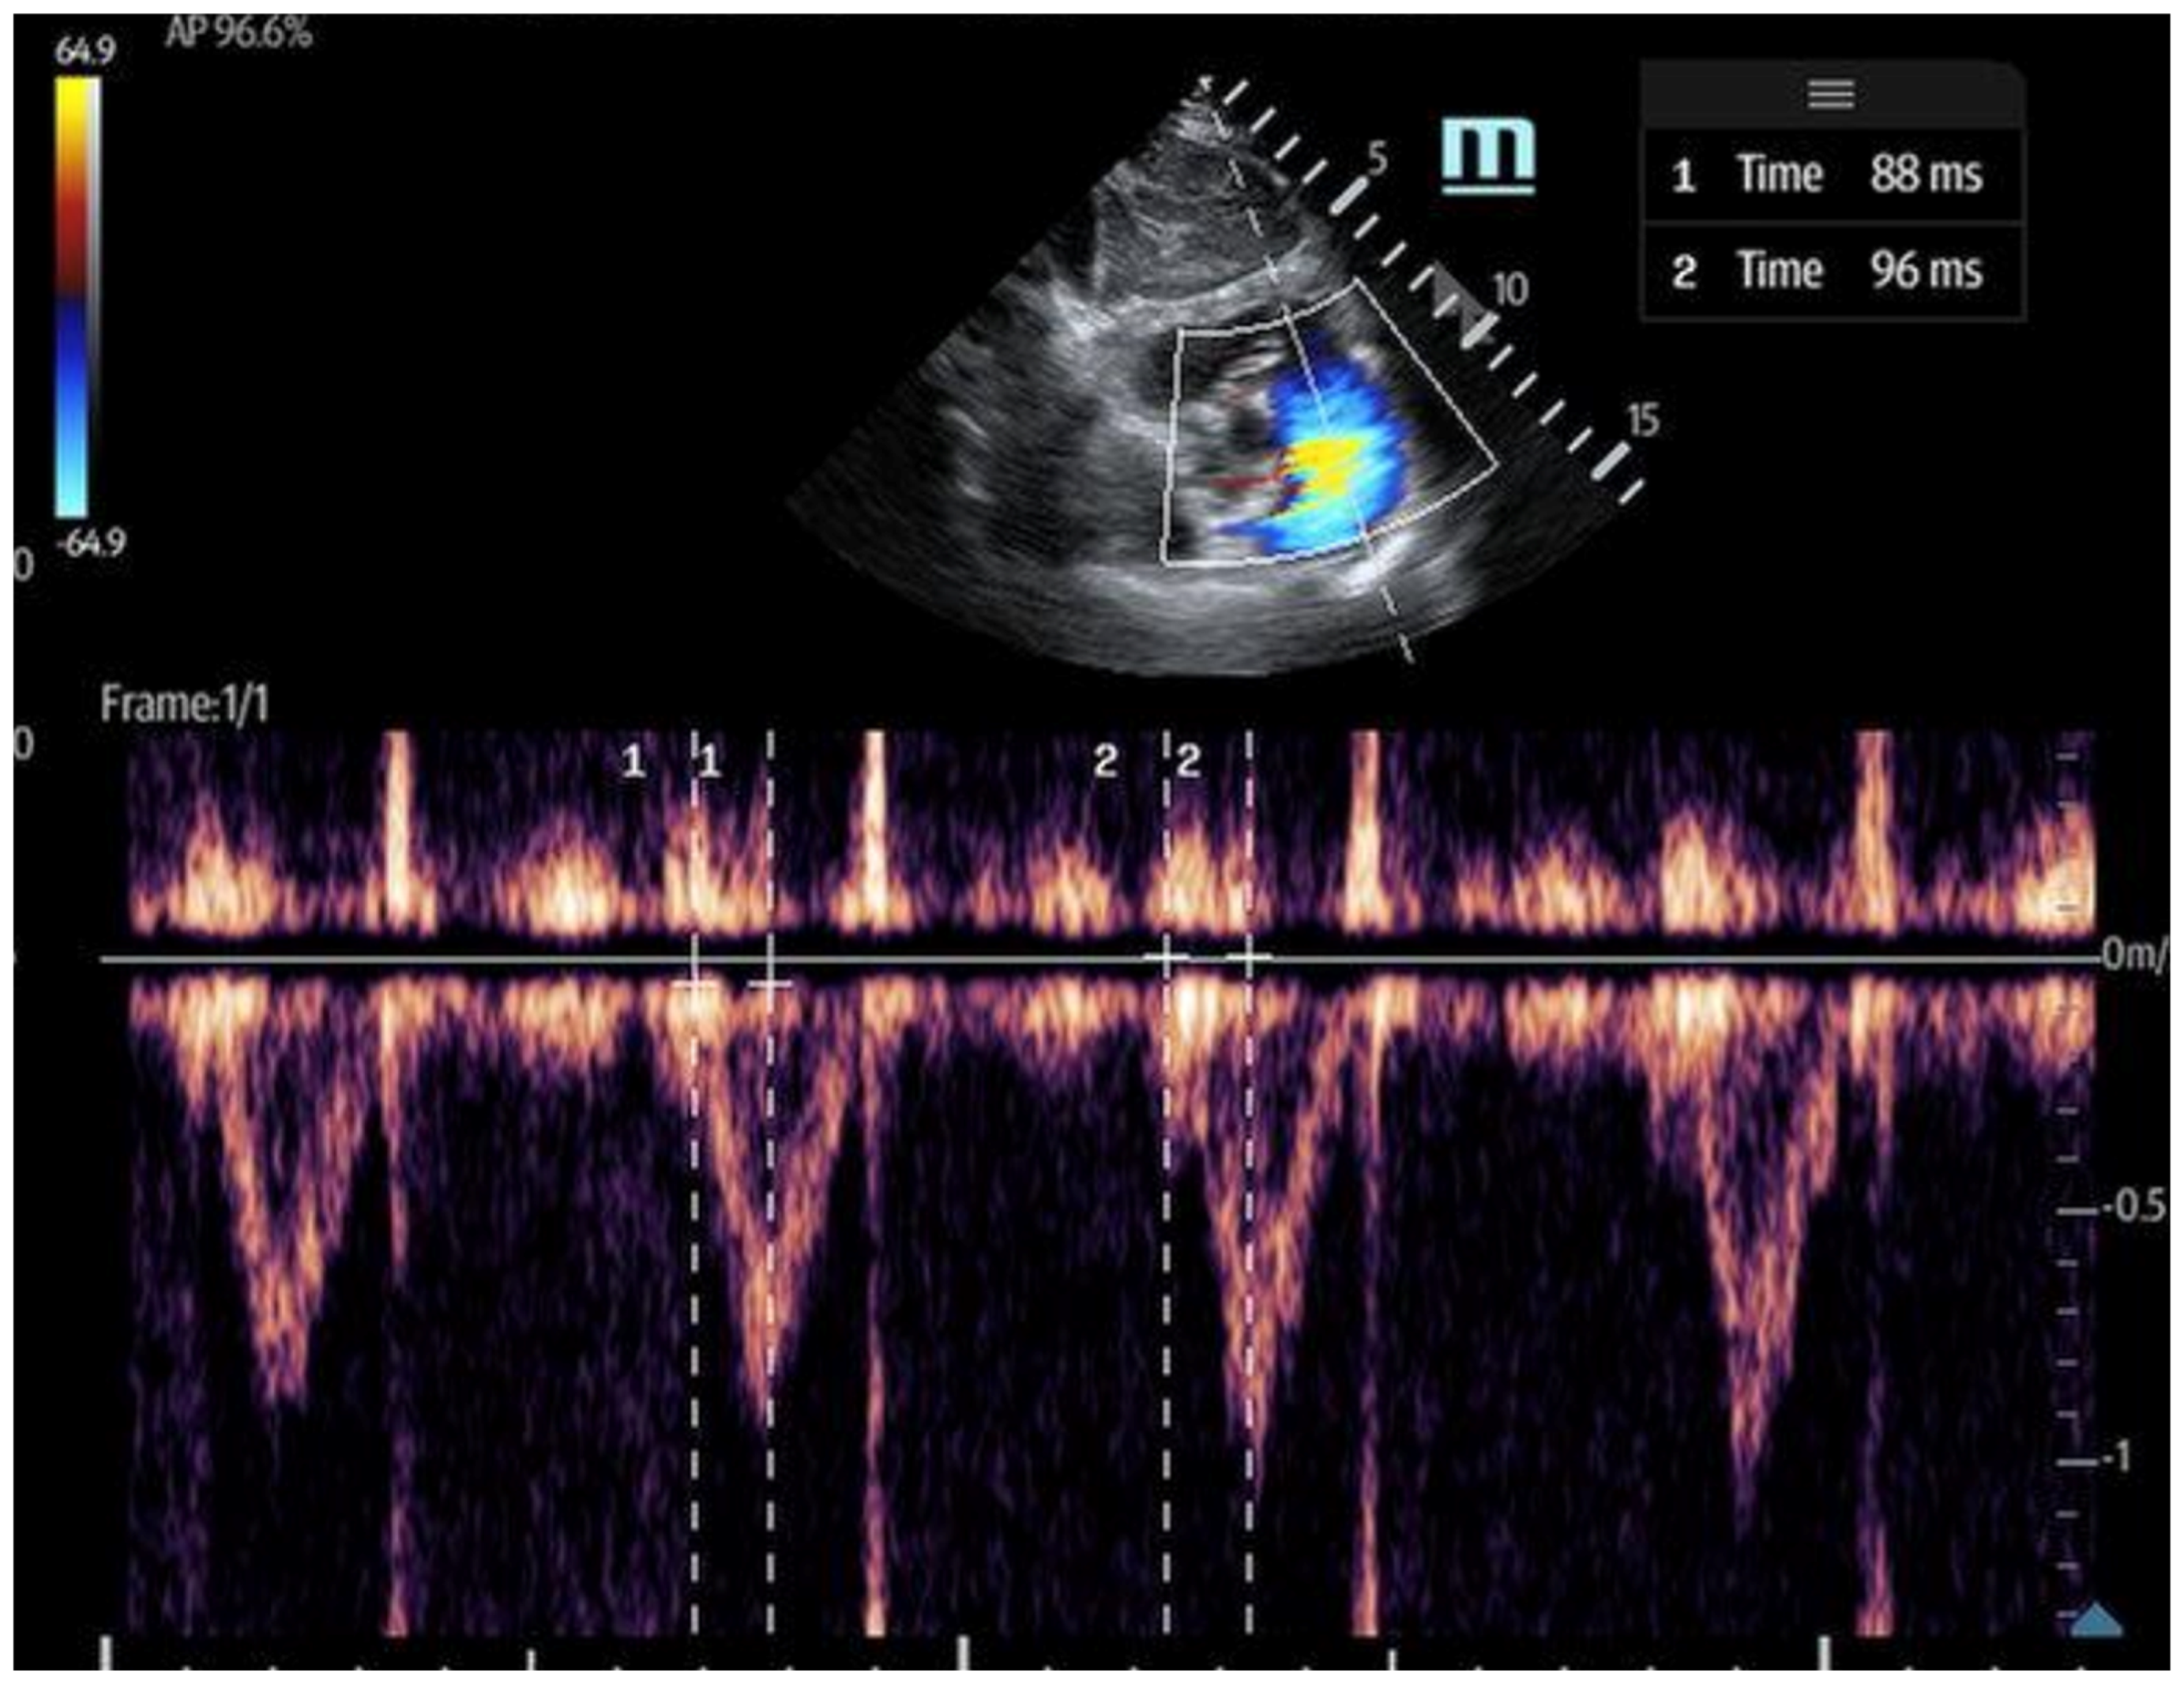

- The 60/60 sign: This is an echocardiography sign that refers to the presence of both pulmonary acceleration time (PAT) ≤60 milliseconds (Figure 9) and tricuspid pressure gradient ≤60 mmHg as a marker for acute RV strain in acute PE, although it has poor sensitivity [52]. It is thought to be more advantageous than McConnell’s sign due to its objectivity and reproducibility [50]. The 60/60 sign has a sensitivity of 36% and a specificity of 94% when seen in combination with McConnell’s sign, emphasizing the utility of various ultrasound findings when assessed in conjunction with each other [50].

Figure 9. Pulmonary acceleration time (PAT) measured in the subcoastal short axis, and PW doppler activation measured as the interval between the onset of pulmonary flow and peak velocity.